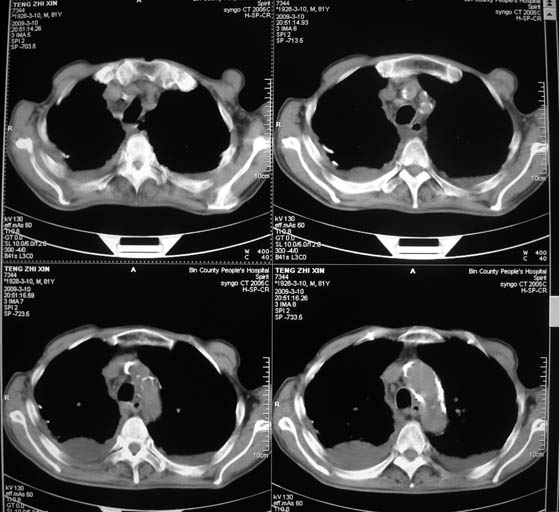

标题: CT18642:男,81岁,发热待查。

男,81岁,发热待查,右侧是占位还是膈疝?

1)考虑右肺下叶中央型肺癌并左肺转移。2)两肺上叶结核(陈旧性)。3)双侧胸腔积液。4)腹水。

右中央型肺癌并双肺及胸膜、肝脏转移

支持,肿块巨大,内有钙化\\坏死,肺肉瘤要考虑

右中心型肺癌并双肺及胸膜、肝脏转移!

很明显的排除膈疝。考虑右肺中央型肺癌,建议增强。胸腔恶性胸水。